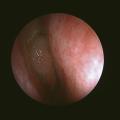

Polypose nasosinusienne

La polypose nasosinusienne est une rhinosinusite diffuse caractérisée par la présence de polypes bilatéraux dans les cavités nasales venant du massif ethmoïdal. Sa physiopathologie repose sur une inflammation chronique de la muqueuse des cavités nasales et sinusiennes marquée par une infiltration éosinophilique plus ou moins…